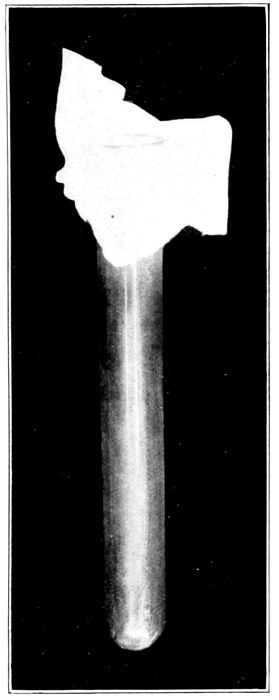

195 |

| |

| 85. |

The Naegele perforator |

196 |